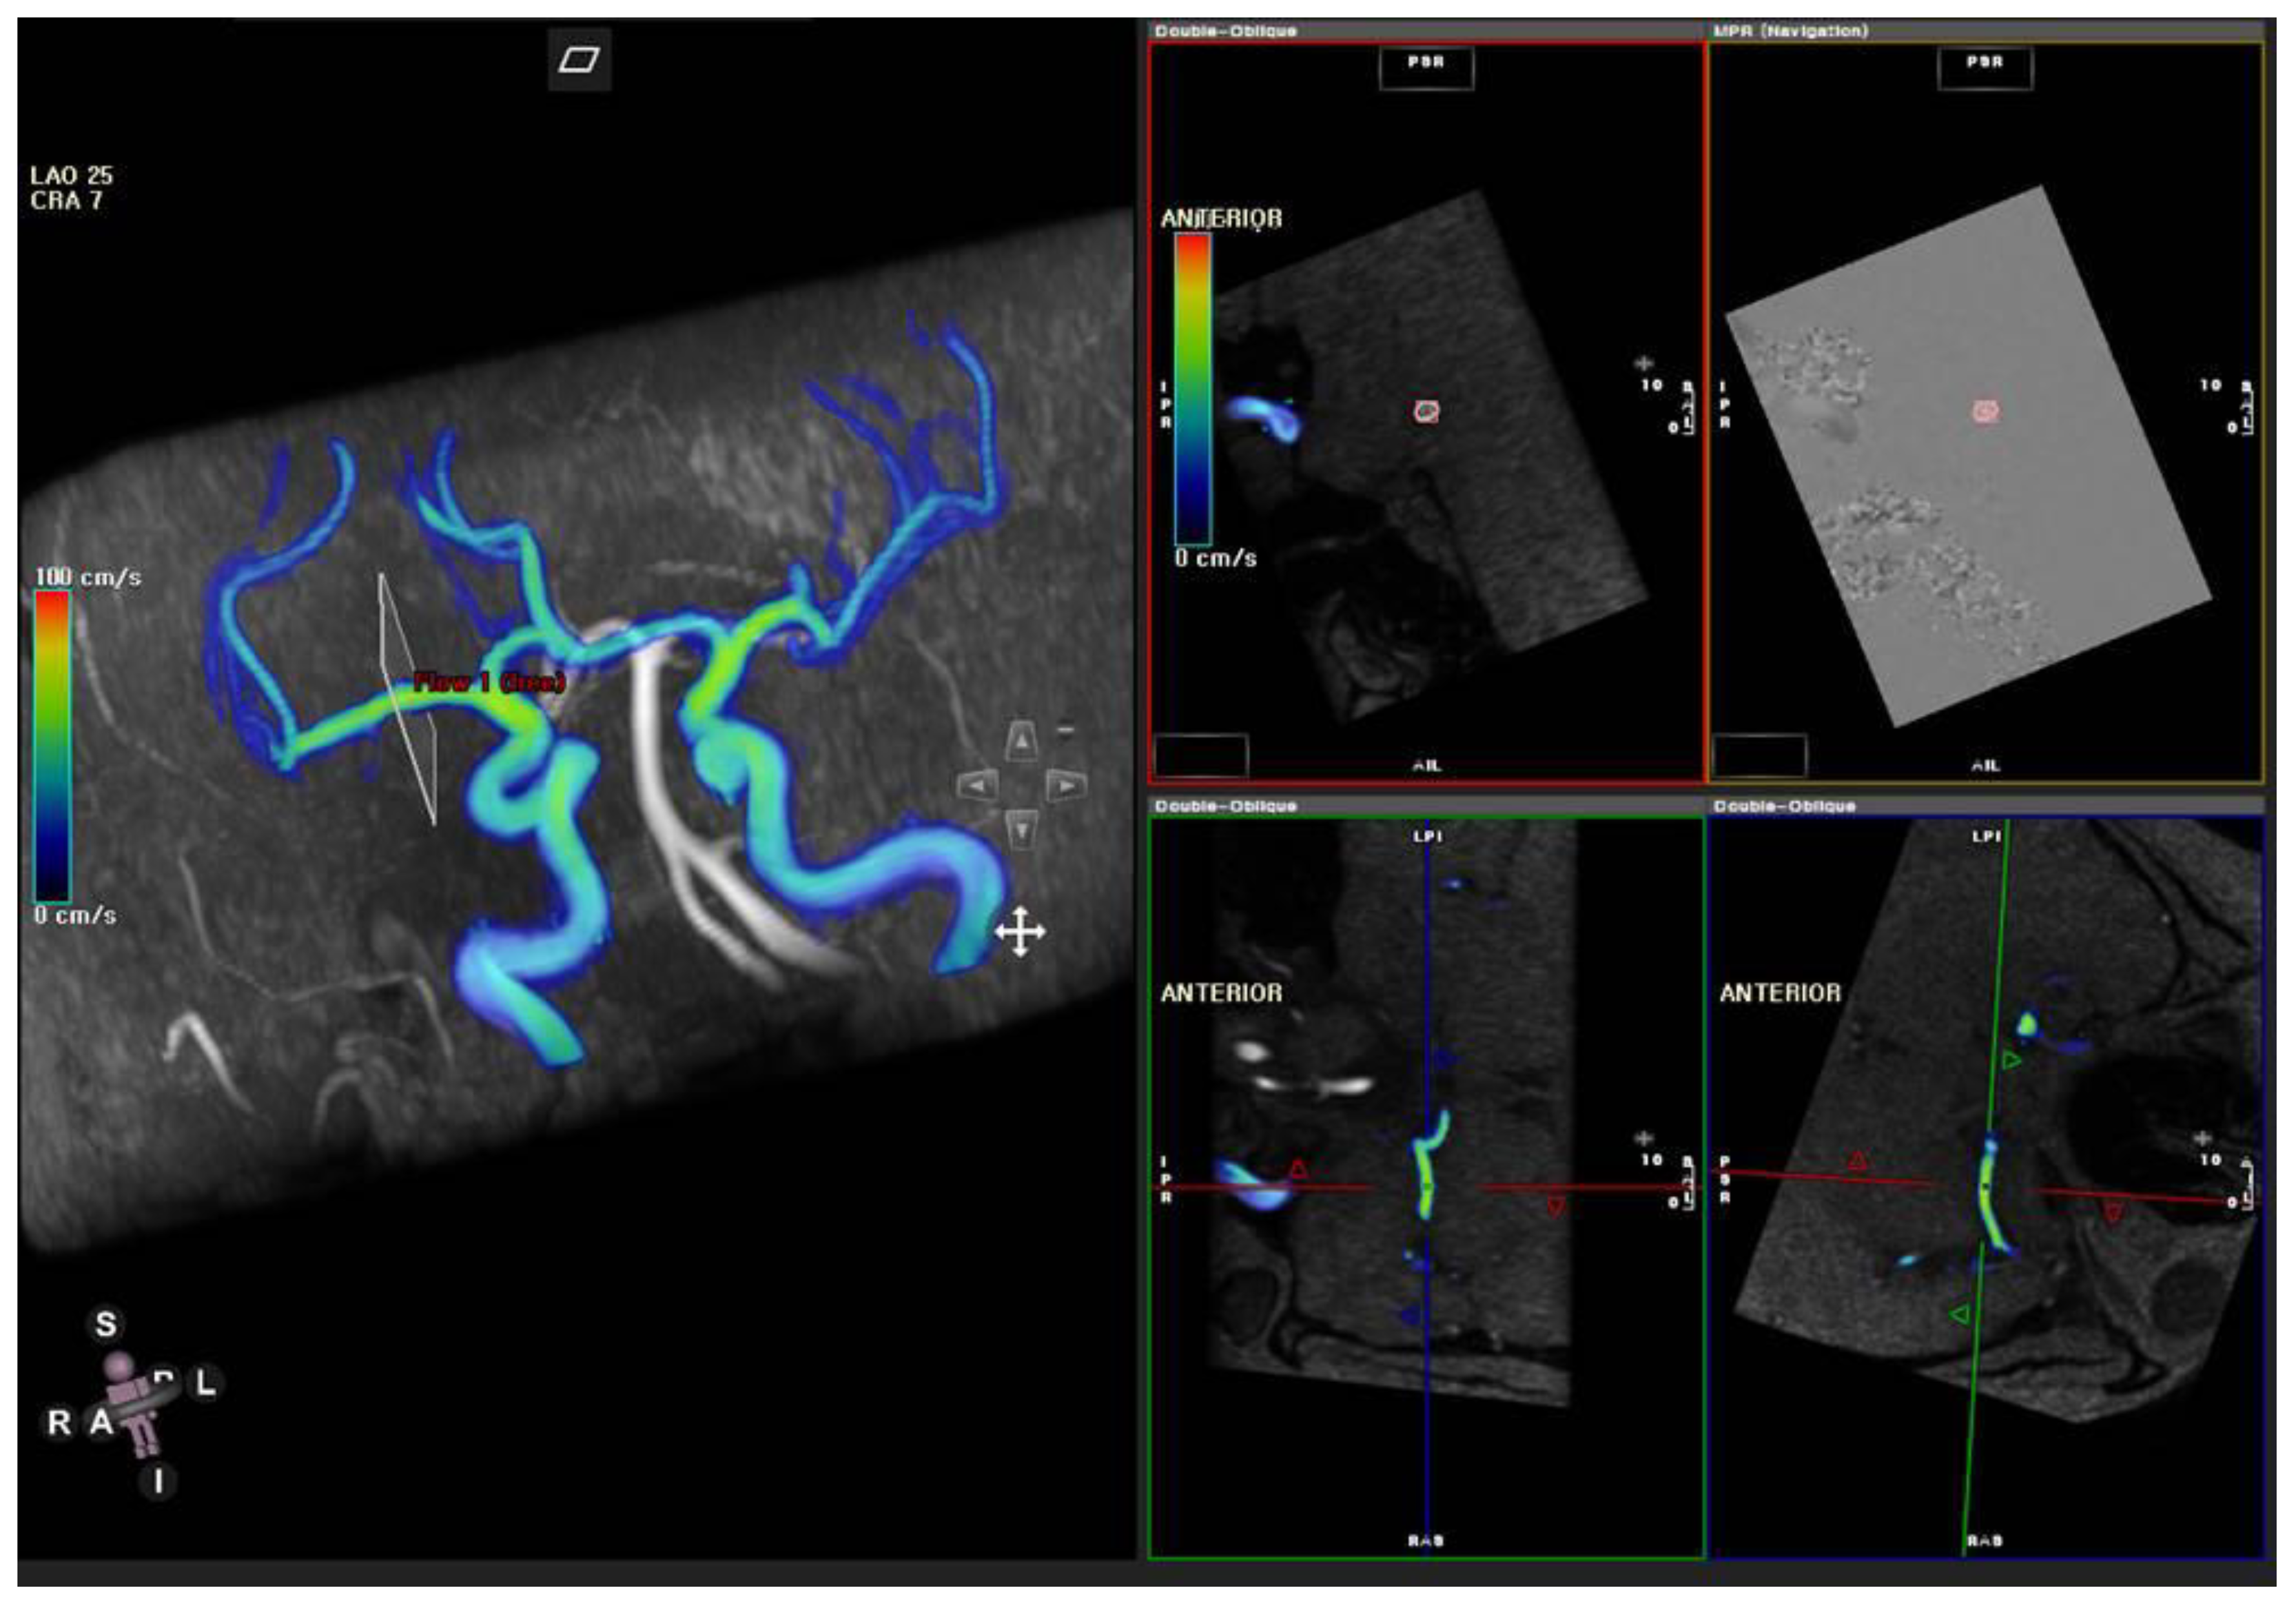

2.4. MR Flow Velocity Analysis